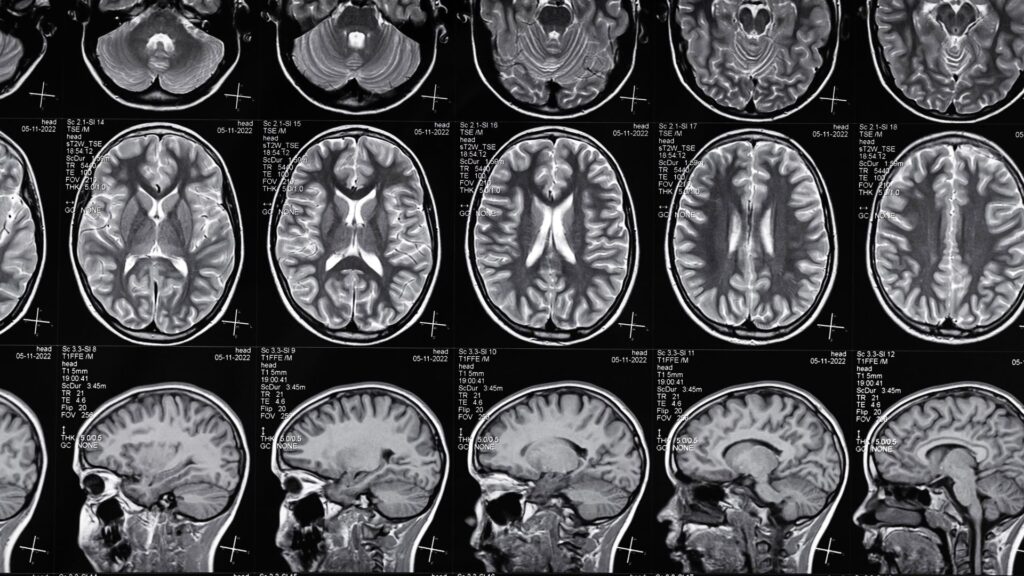

Not all serious injuries display immediate symptoms, especially those affecting the brain. While many accident victims feel disoriented or shaken following the incident, lingering symptoms may point to something far more severe–Traumatic brain injuries (TBIs). These conditions can develop subtly and worsen over time, even escaping medical notice until complications arise. If your injury was caused by someone else’s negligence, documenting symptoms and seeking immediate medical attention could make all the difference in a brain injury legal claim.

Brain injuries can manifest as numerous symptoms, determined by the trauma’s severity. Whether mild or severe, these injuries require prompt medical attention and careful documentation to protect your health and build a strong legal case.